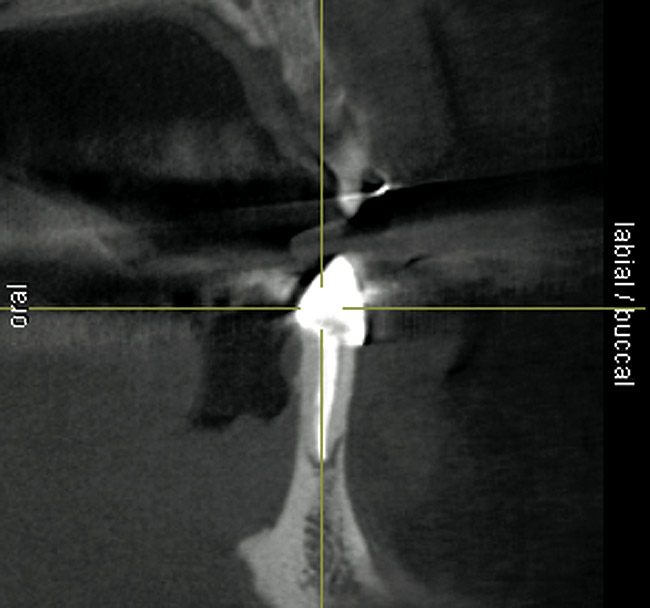

Figure 19  Scanning appliance worn by the patient for CT scan (Fig 19). Fabrication of a surgical template for flapless, computer-guided implant placement would be based on digital information obtained from the scan. Fig 20 demonstrates the cross-sectional view of the No. 8 position. Planning software demonstrated adequate 3-D volume for implant placement in this regenerated area where rhBMP-2/ACS and mesh were combined.

Figure 20  Scanning appliance worn by the patient for CT scan (Fig 19). Fabrication of a surgical template for flapless, computer-guided implant placement would be based on digital information obtained from the scan. Fig 20 demonstrates the cross-sectional view of the No. 8 position. Planning software demonstrated adequate 3-D volume for implant placement in this regenerated area where rhBMP-2/ACS and mesh were combined